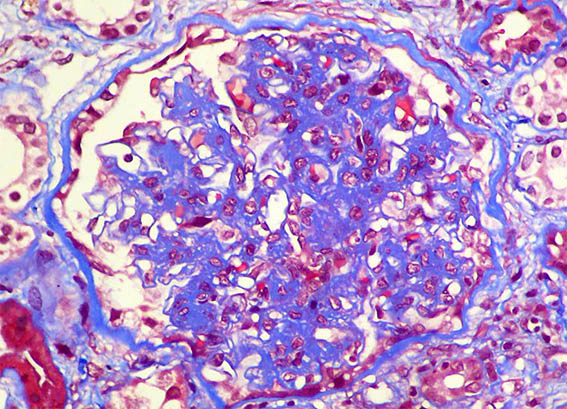

Figure 3. Masson's trichrome stain, X400.

Figure 4. Masson's trichrome stain, X400.